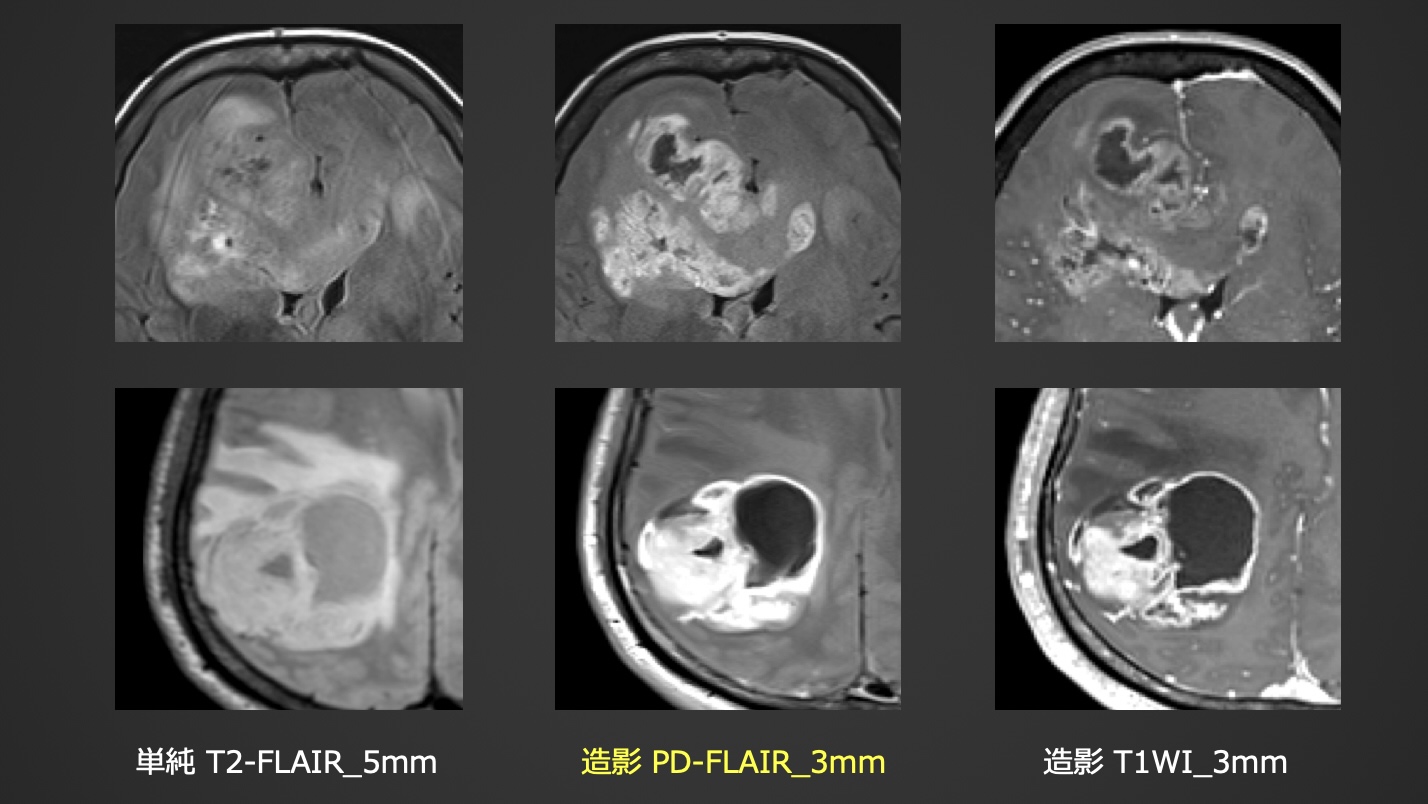

初発膠芽腫2例:TE短縮による浮腫コントラスト低減と造影効果上昇により、腫瘍周囲の微小濃染や、壊死組織内へのGd流入の様子を観察できた2症例。